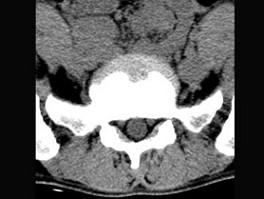

问题 男,29岁,腰痛伴下肢轻度麻木,有外伤史,请结合所提供图像,选择最佳答案 ( )

选项 A、S向后滑脱 B、未见异常 C、L向后滑脱 D、S向前滑脱 E、L向前滑脱

答案 E